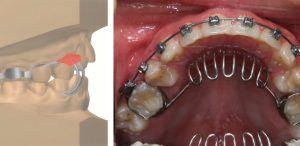

Tratamiento de la mordida abierta anterior severa mediante trampa lingual y extracción dental

Directo del Journal BMC Oral Health, les traemos un artículo llamado Treatment of severe anterior open bite by using tongue crib and teeth extraction: a case report. Es un reporte de caso, el cual se centra en un adolescente varón de 13 años de edad con mordida abierta anterior de 6 mm, maloclusión de Clase … Sigue leyendo Tratamiento de la mordida abierta anterior severa mediante trampa lingual y extracción dental